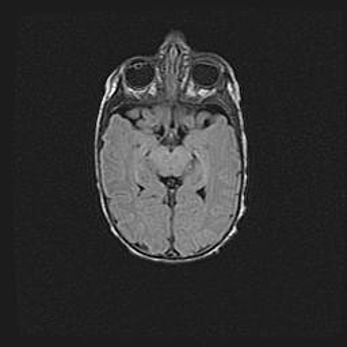

Множественные кисты обоих полушарий головного мозга, наибольшая из них в правой затылочной области. Ассиметричная атрофическая гидроцефалия.

Возраст: 7 месяцев

Вес: 5660 г

Пол: мужской

Окружность головы: 41,5 см

Срок гестации: 28-29 недель

Кисты головного мозга развиваются в результате многоочаговых некрозов вещества мозга и возникают вследствие перенесенной перинатальной инфекции, менингитов, энцефалитов, асфиксии, родовой травмы, расстройств мозгового кровообращения различного генеза. Образованию кист в веществе головного мозга плодов и новорожденных способствуют такие факторы, как высокое содержание в нем воды, недостаточная (или отсутствие) миелинизация и слабая астроглиальная реакция на повреждение.

Кисты могут сочетаться с гидроцефалией и другими поражениями головного мозга.